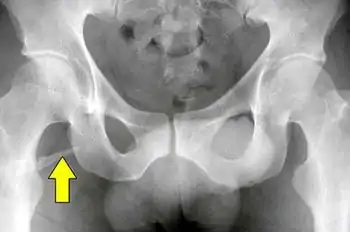

Radiograph showing a pelvic digit

A pelvic digit, pelvic finger, or pelvic rib is a rare congenital abnormality in humans, in which bone tissue develops in the soft tissue near the pelvis, resembling a rib or finger and often divided into one or more segments with pseudo-articulations. Pelvic digits are typically benign and asymptomatic, and are usually discovered accidentally. Approximately 41 cases have been reported.[1]

The pelvic digit was first reported by D. Sullivan and W.S. Cornwell in 1974.[2] Pelvic digits may be located at any level of the pelvis, the lower ribs, or even the anterior abdominal wall. It is theorized that pelvic digit anomalies arise during the mesenchymal stage of bone growth, within the first six weeks of embryogenesis. Their formation may result from a failure of the primordium of the coccyx to fuse to the vertebral column, leading to the independent development of a proto-rib structure.[1]